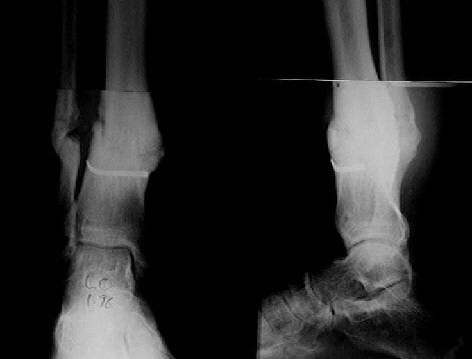

Female. 65 years old. 2 years ago trimalleolar fracture left ankle. First ORIF failed. Second ORIF with autologous graft at the fibular fracture was complicated by infection. The X-ray pictures show the actual situation. What are the suggestions of the group?